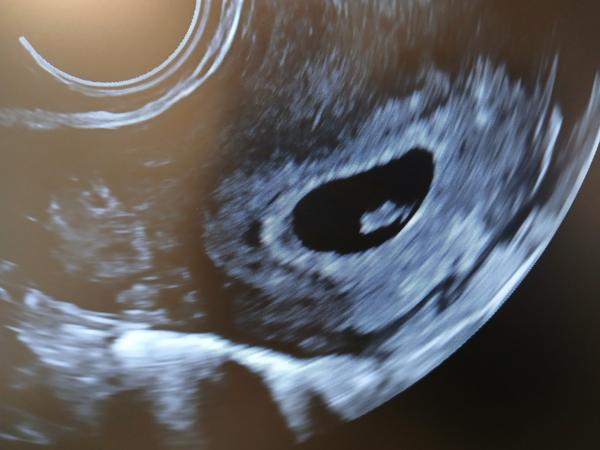

Poprosim o radu. Vcera tj 27dc jsem si delala tt. (Vysel mi viz obrazek) Mamatest delany odpo. Poté jsem zkusila test od Dr. Maxe a na nem bilo. Je mozno nejaka sance ze by to mohlo byt uz konecne vyjit? Test mi nikdy predtim pred ocekavanou ms nikdy nic takoveho neukazal 🙂 dekuji moc za odpovedi 🙂

@bobinka989 Mě mamatest vyšel včera takhle takze taky čekám za pár dnů jestli se to vybarvy víc nebo ne

Ahoj, prosím o radu. Předevčírem mi vyšel mamatest s duchem, včera ráno negativní digitální Clearblue, dnes ráno negativní da vinci pharma test (s tím zkušenosti nemám, nic jiného neměli v lékárně). Může se jednat o biochemické těhotenství nebo spíš falešný výsledek mamatestu? Děkuji. Přikládám foto mamatestu.